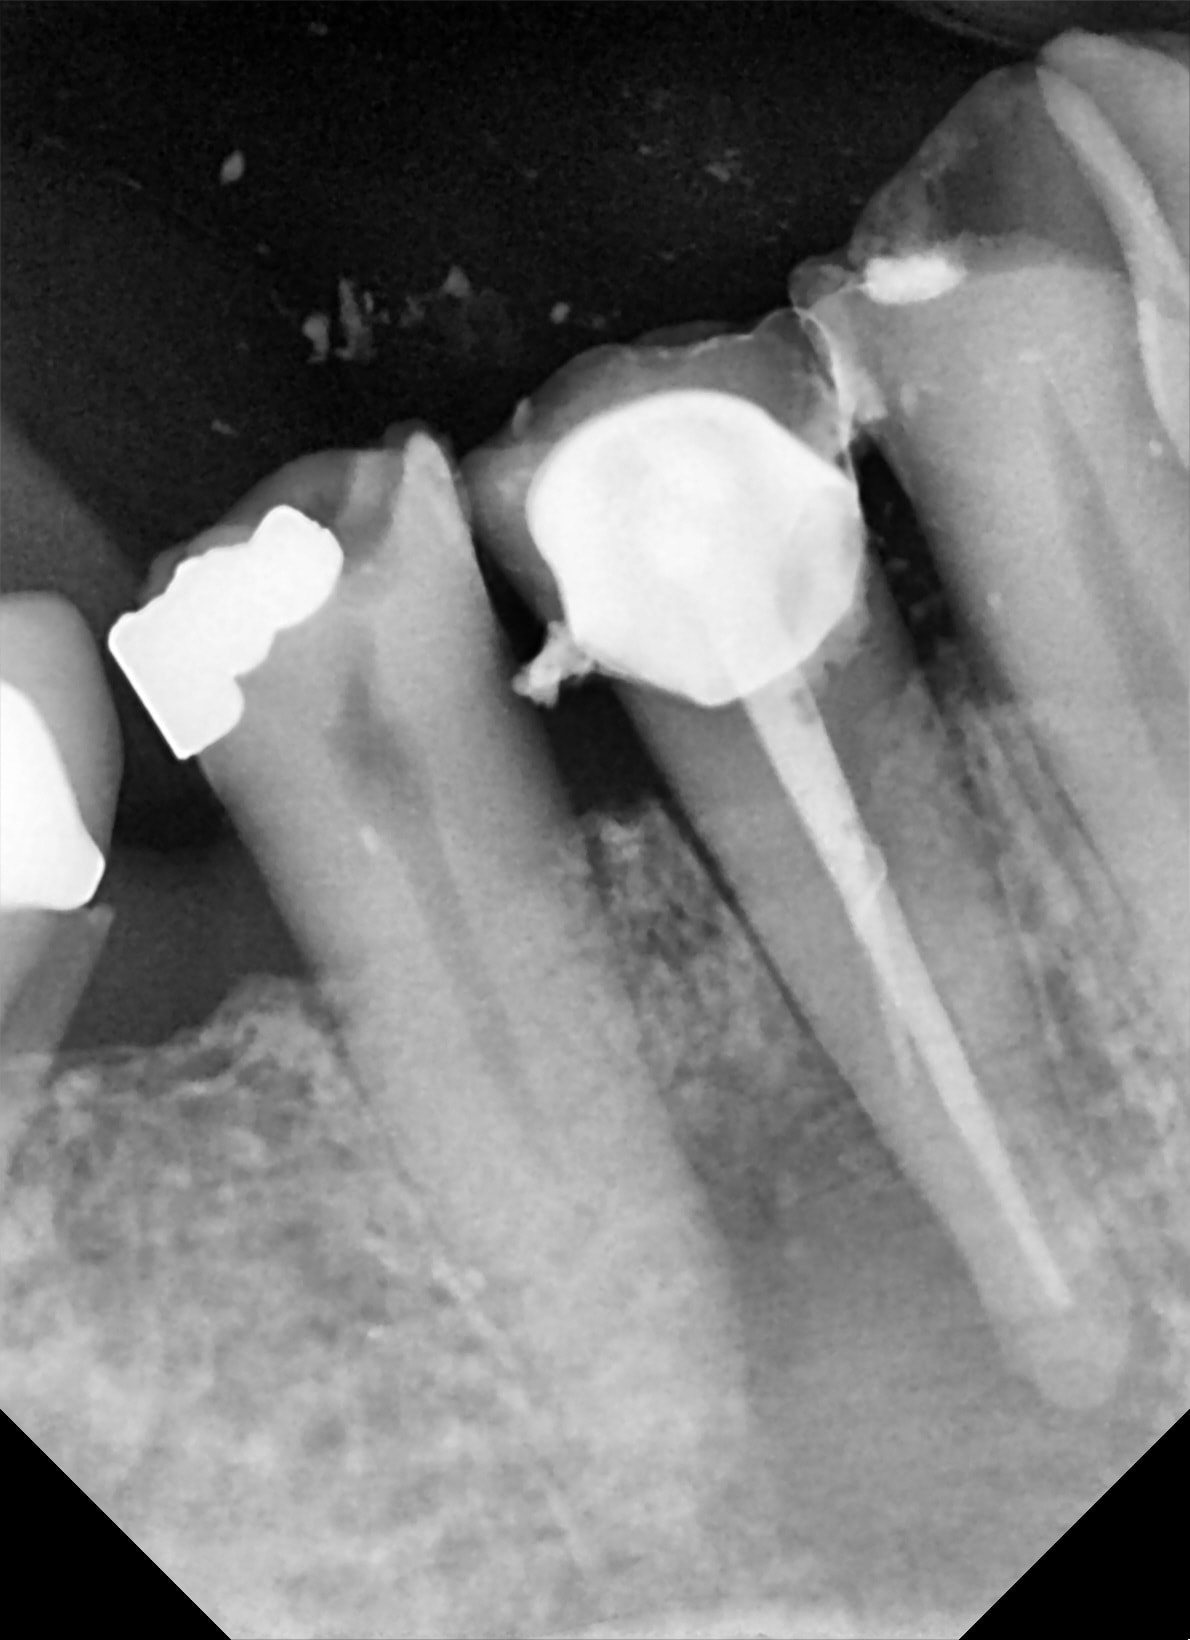

Alors j'ai fais l'endo début janvier , ça allait mieux , mais il restait toujours une petite tuméfaction au palais , je me suis dit vas-y casa tu l'as déjà fait ...! donc fin janvier , j'ai extrait le dent , retouché un peu l'apex , un petit crochet inesthétique ! ,cureté le fond de l'alvéole ..et j'ai remis avec une provisoire sans contention rien ... j'ai vérifié en Mars je crois , tout allait bien , plus rien au palais , en mai j'ai fait la définitive ....impeccable ! aucune mobilité gencive impeccable !

J’ai fait avec une monoraduculée , avec 2 racines , avec une triradiculée... du coup J’essaie désespérément de trouver un cas avec un bridge . On enlève le bridge et les dents puis on remet les dents piliers et le bridge qui va avec comme si de rien n’était.

bien justement la voilà la 37 , je l ai vu aujourdhui .

la radio est belle , , je n' arrive pas a la mettre dessus avec ces putains de enregistrer sous , sous quoi ? je ne sais pas ,

bref tu peux me faire confiance , et en photo ça donne ça .

la gencive est belle et j'ai pris l empreinte .

l'affaire est dans le sac !

merci enlaye!

extraction -> resection apical -> reimplantation ?